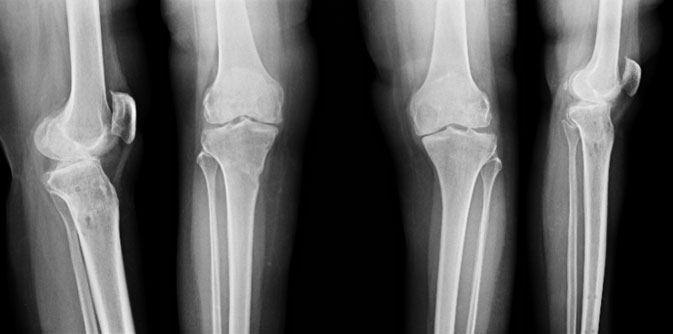

| 6 months post surgery |

| The X-rays 6 months after high tibial osteotomy, showing excellent correction of the right side, with maintenance of joint space. The left side is also troubling her, and is scheduled for surgery soon. |